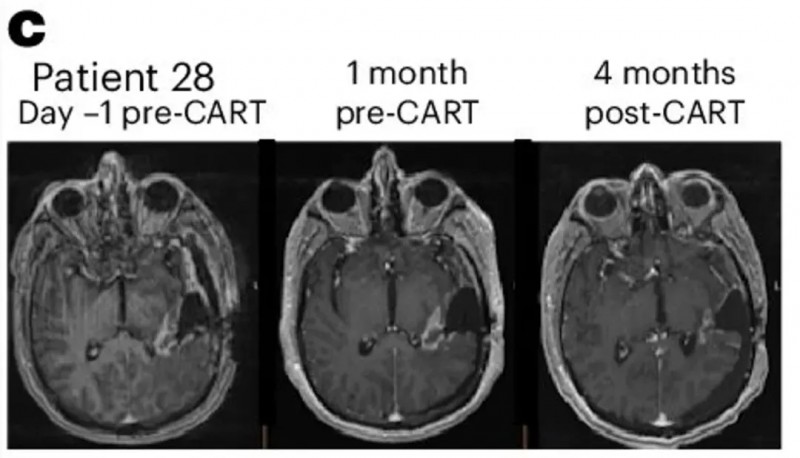

值得一提的是,其中患者28的T1加权对比MRI图像尤为值得关注,其疗效已通过mRANO标准确认达到部分缓解(PR,详见下图)。

▲图源“Nature Medicine”,版权归原作者所有,如无意中侵犯了知识产权,请联系我们删除